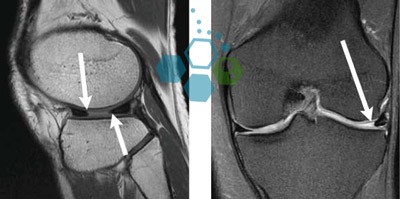

Targeting Medial Collateral Ligament (MCL) Injury

The Regen Center ACL protocol is a combination therapy using enhanced cells and osteogenic growth factors for autoimmune knee arthritis. MSC+ cells are also used to heal partially torn Anterior cruciate ligaments and complete non-retracted ACL tears. Our safe non-surgical alternative to repair ACL is a very viable option for those considering surgical intervention because of a partial ACL tear or complete non-retracted tear.

Enhanced Stem Cells can help you avoid extended downtime and the painful rehabilitation process that traditionally follows after anterior cruciate ligament surgery. For severe or complex injuries, our orthopedic team will need to target the injured zones using sophisticated image guidance to ensure optimal delivery of the cells for a successful minimally invasive procedure.

Stem Cells for Treating Bucket Handle Tears

A medial meniscus Tear: The Medial menisci can be found in the inner side of our knee joints. The torn medial meniscus diagnosis usually describes the severity of tear on the medial meniscus that is often caused by traumatic injury or sudden change of force or direction that occur in sports such as skiing, basketball, football, soccer, and volleyball. This type of injury can also occur due as a result of repetitive use injuries like long-distance running, track and field, and cycling along with long term degenerative knees in older patients. Stem cell therapies can treat medial meniscus tears and cartilage damage very efficiently and without the need for surgical intervention.[4]